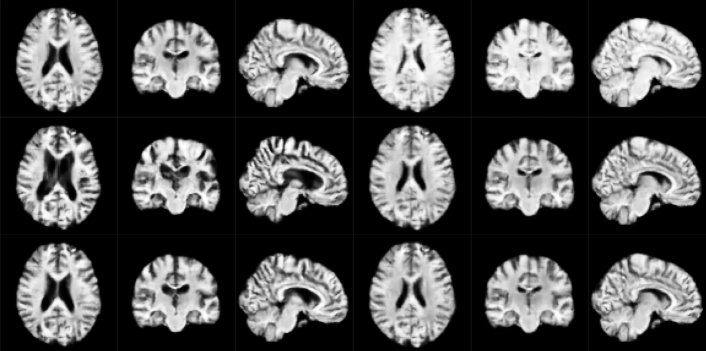

Qualitative analysis of the compared methods reveals that samples from VAE are not anatomically correct in many cases and display regions that appear scrambled. WGAN generates anatomically viable samples, however in many of them the cortical folds do not follow the anatomical structure. Additionally, as in VAE, samples exhibit regions where artifacts are dramatically different from the rest of the volume. Samples from our model are the most anatomically correct due to starting from the fixed template. However, the samples occasionally have a wavy visual quality due to improperly generated random deformation fields at finer scales. We furthermore observe a lack of sufficient topological diversity in the cortical folds. Samples for each of the above methods are shown in Section A of Supplementary Material.